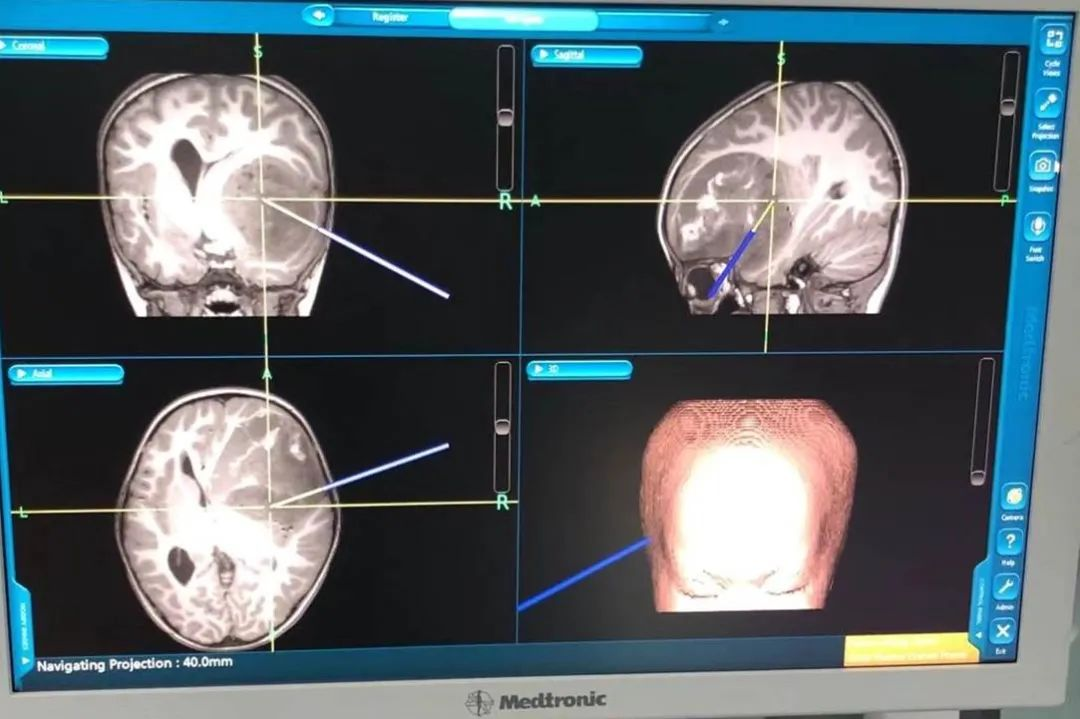

拟定手术方式

右侧额颞叶占位切除;

仰卧位、头钉固定;

右侧额颞顶部弧形切口;

术前导航定位病变具体位置。

术前导航